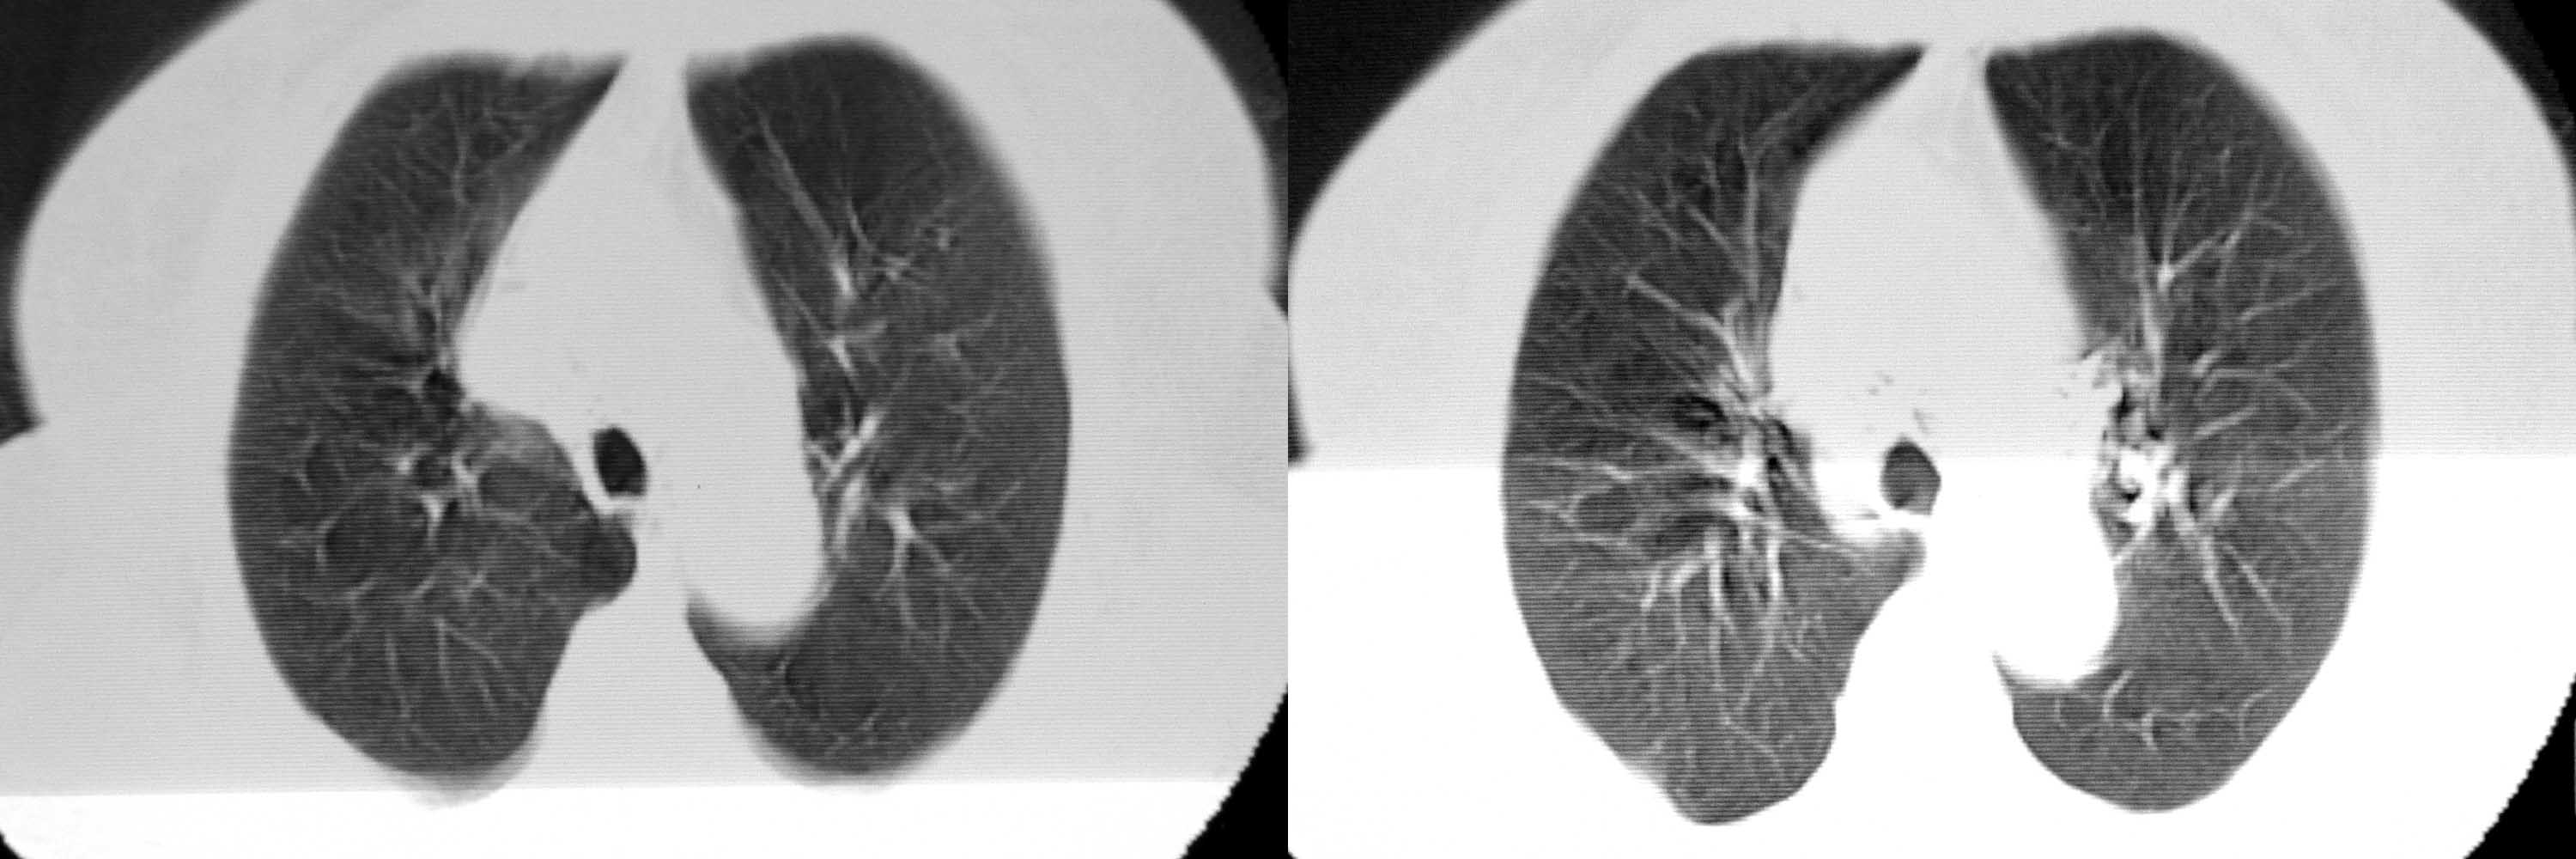

女78岁咳嗽咳痰无咳血平片报右上肺不张、慢支、肺气肿、请老师们帮忙看看,箭头所指是什么?是占位吗?有肺气肿吗?谢谢

箭头所指考虑血管影;纵隔内及双肺门区多发淋巴结钙化;不支持肺气肿。

箭头所指考虑血管影(头臂血管);纵隔内及双肺门区多发淋巴结钙化;不支持肺气肿。